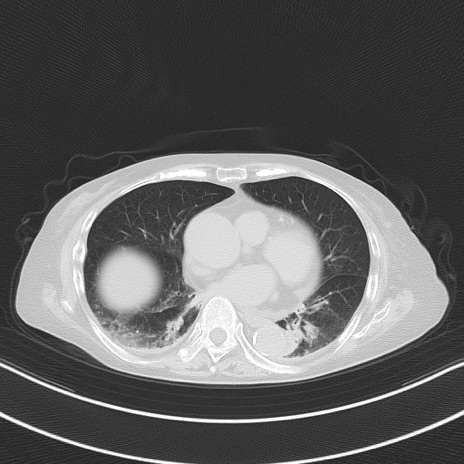

横断像

他院CT